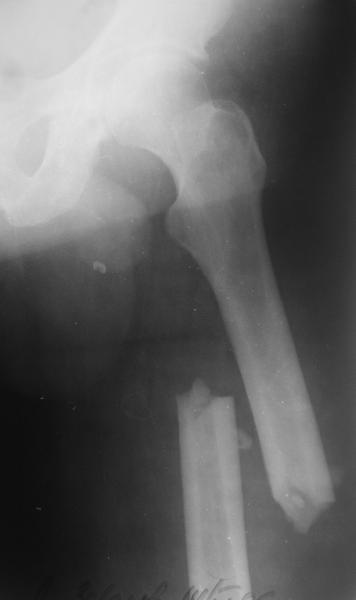

Изначально была выбрана не правильная точка введения стержня, в связи с чем в конце, я подчеркну, в конце операции произошло из-за напряжения между прокимальным концом канала бедра и стержнем разрушение в/3 бедра.

Проволока наложена потому, что при введении штифта не прошли эту зону римером и произошли сколы на концах отломков.

Под ЭОП во время операции такого смещения не было. Мы бы конечно не отпустили этого больного с такой картиной (сами бы что-то сделали или к вам отпр).

Очевидно была неправильно, причем, очень неправильно! точка введения штифта.